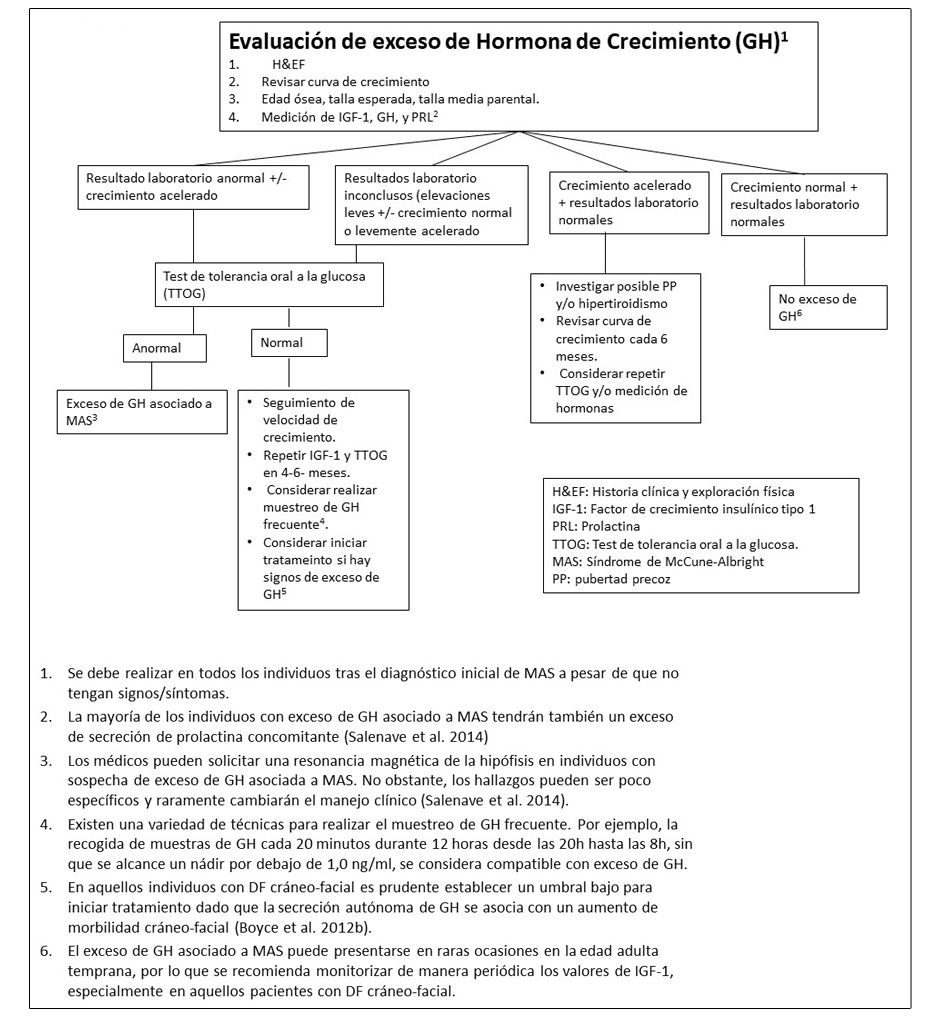

Figura 5. Pruebas y seguimiento recomendado para la evaluación del exceso de hormona de crecimiento en individuos con Displasia Fibrosa / Síndrome de McCune-Albright

Exceso de producción de hormona de crecimiento.

Aproximadamente un 15-20% de los individuos con DF/MAS son portadores de la mutación GNAS patogénica en la hipófisis anterior lo cual puede resultar en la producción autónoma de hormona de crecimiento (GH). Se estima que el 80% de los individuos que presente exceso de GH también presentarán hipeprolactinemia de manera concomitante (Salenave et al 2014).

El exceso de GH en individuos con DF/MAS suele manifestarse inicialmente con aceleración del crecimiento lineal y pueden llegar a desarrollar características de acromegalia. Clínicamente, el exceso de GH debe diferenciarse de la pubertad precoz y del hipertiroidismo, los cuales también se asocian a una aceleración en el crecimiento lineal.

El exceso de GH no tratado se asocia con la expansión de las lesiones de DF en la región cráneo-facial resultando en macrocefalia y un riesgo aumento en la pérdida de agudeza visual (Boyce et al 2013) (ver Figura 2B).